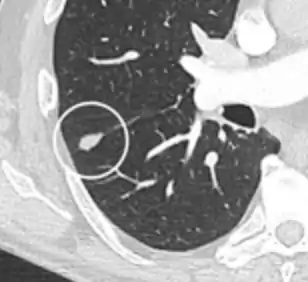

Lung nodule abutting a pulmonary cyst.[9]

• A lung nodule abutting a pulmonary cyst is a rare finding, yet indicating cancer.[9]